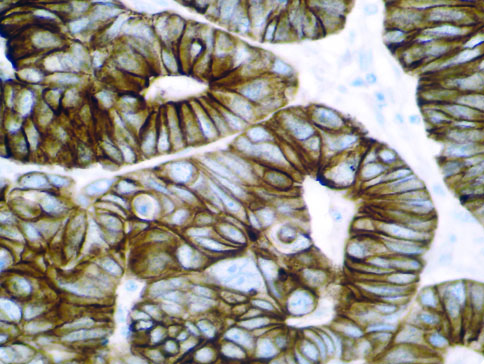

The first cytokines released are interleukin 1β (IL-1β) and tumor necrosis factor-α (TNF-α), which attract a variety of circulating white blood cells (WBCs) to the infection site, including neutrophils, monocytes, macrophages, and natural killer (NK) cells. This response, along with the antipathogenic chemicals released by these cells (i.e., complement), comprise the innate immune response. These cells directly attack the invading pathogen and also release additional cytokines, chief among them interleukin-1 and 6 (IL-6). IL-6 is essential for invoking the adaptive immune response, which calls T-cells, B-cells, and T helper (Th) cells to the infection site. IL-6 also stimulates further recruitment, proliferation and activation of macrophages.

This activation induces inflammatory monocytes to highly express IL-6, starting a localized and then systemic cascade effect that results in hyperproduction of IL-6, which accelerates the inflammatory process. Because IL-6 also increases vascular permeability, excessive levels cause blood vessels to become very leaky. This, along with clotting factors released from vascular endothelial cells, stimulates the coagulation cascade, resulting in microthrombosis (tiny clots), which leads to ischemia and tissue death of the kidney, intestines, heart, liver, brain and extremities.